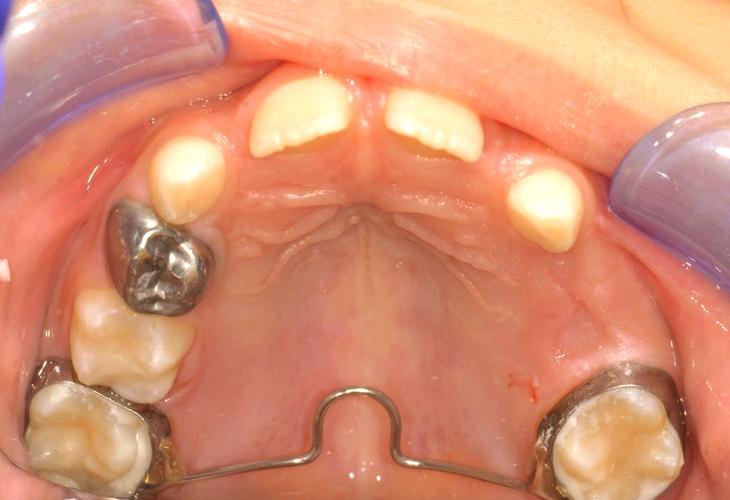

灵长间隙通常出现在乳牙列的乳尖牙与第一乳磨牙之间,上颌较下颌更为常见,发生率约为70%-80%,其形成与乳牙、恒牙的大小差异直接相关:乳磨牙牙冠宽度大于同位置的恒前磨牙,两者之间的差值即为“灵长间隙”,上颌乳尖牙与第一乳磨牙的总宽度约为21mm,而对应的恒尖牙与第一前磨牙总宽度约为19mm,两者差值约2mm,这部分多余的间隙便构成了灵长间隙。

- 视诊与触诊:观察乳尖牙与第一乳磨牙间是否有肉眼可见的间隙,用探针或探针轻轻感受牙间隙大小,初步判断间隙是否充足。

- 模型分析:制取牙列模型后,用游标卡尺测量乳尖牙与第一乳磨牙近远中径的总宽度,与对应恒牙胚(通过X光片确认)的预测宽度比较,计算差值,正常情况下,上颌灵长间隙应≥1.5mm,下颌≥1mm。

Q2:如何在家判断孩子是否有灵长间隙?

A:家长可通过简单观察初步判断:让孩子张嘴,自然咬合,观察上颌两侧“犬牙”(乳尖牙)与后面的大牙(第一乳磨牙)之间是否有黑色缝隙,若有缝隙,说明存在灵长间隙;若看不到缝隙,且乳牙排列紧密,需及时带孩子到口腔正畸科检查,通过专业测量确认间隙情况,若乳牙早失(如牙齿脱落超过3个月未萌),也需尽快就医,防止间隙关闭。